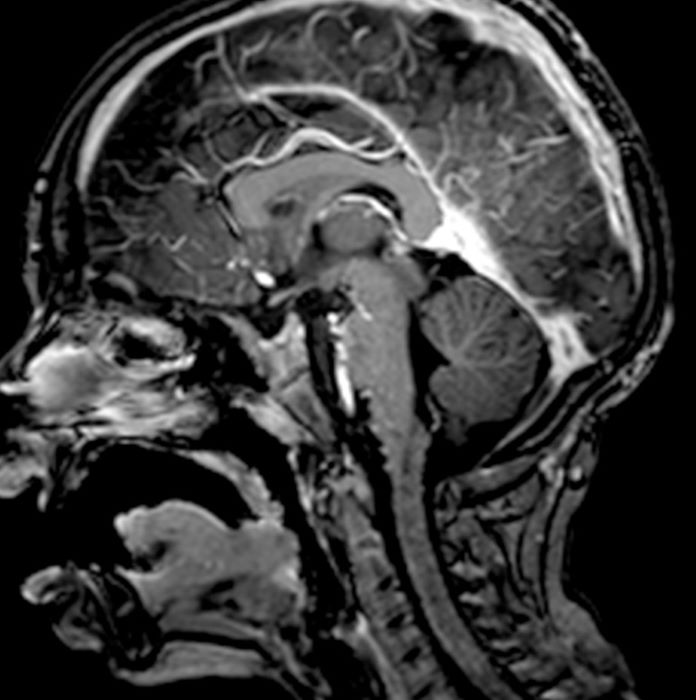

Пустое турецкое седло симптомы у женщин

Пустое турецкое седло симптомы у женщин 111 фото